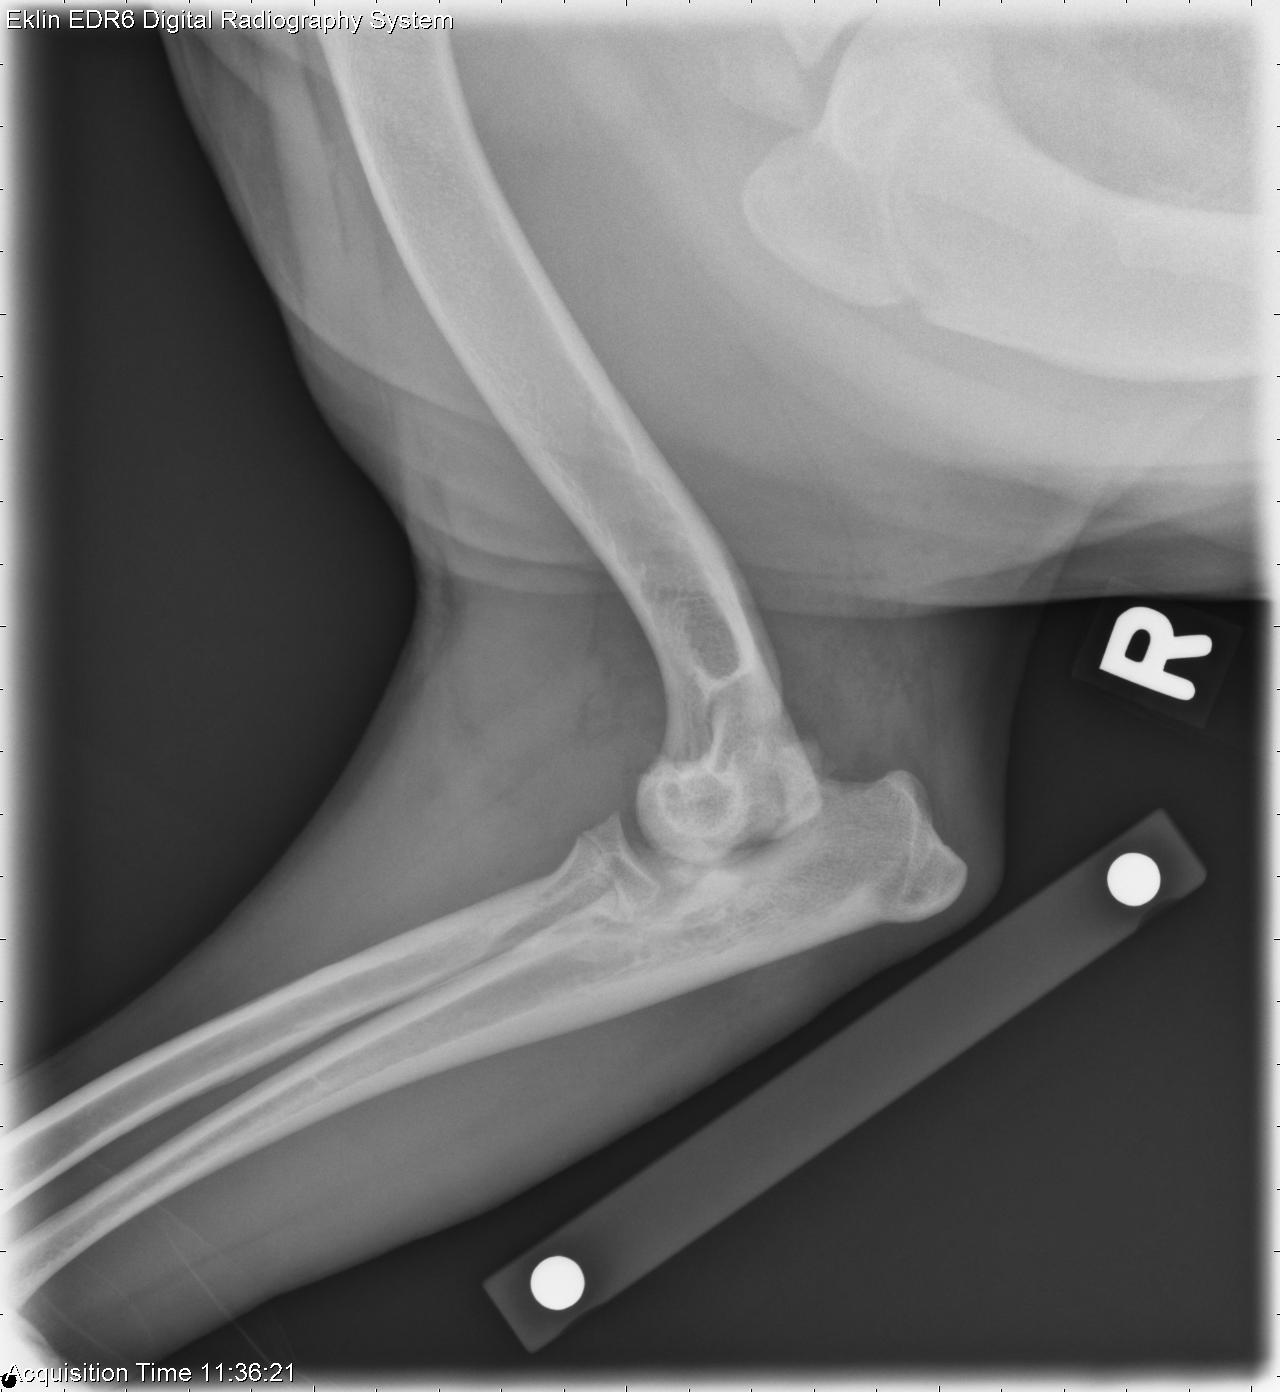

Case of the Day

Pyothorax

Contributed by Allison L Zwingenberger

Pleural effusion with pleural thickening is indicative of pyothorax. The cranial lung lobes are likely atelectic. Mild pneumothorax may be iatrogenic or secondary to pulmonary rupture or abscessation.

Thoracic fluid cytology - Marked purulent septic exudate with evidence of prior and ongoing hemorrhage consistent with pyothorax. No organisms were cultured.